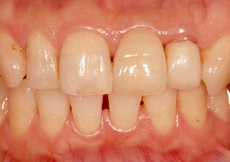

インプラント埋入のケース(前歯)

前歯が折れてしまい、ご来院されました。途中で折れてしまった歯の根を取り除き、インプラントを埋め込みました。前歯でも、ブリッジのように両隣の歯を削ることなく、見た目もキレイに修復することができます。

治療後